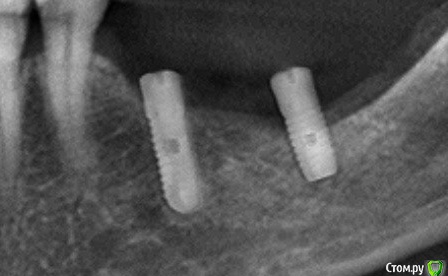

kamranchick Опубликовано 11 января, 2017 Поделиться Опубликовано 11 января, 2017 Господа, подскажите пожалуйста, что за имплантат?установлен 4 года назад, не конмет ли, поставили за 12000р? израильские ключи проворачиваются.и какие формировали подойдут к нему? Ссылка на комментарий

Чертков Александр Опубликовано 12 января, 2017 Поделиться Опубликовано 12 января, 2017 что за имплантат? Астра или аналог Ссылка на комментарий

red_butler Опубликовано 12 января, 2017 Поделиться Опубликовано 12 января, 2017 Астра или аналог установлен 4 года назад поставили за 12000р? голосую за аналог Ссылка на комментарий

red_butler Опубликовано 12 января, 2017 Поделиться Опубликовано 12 января, 2017 это заглушка стоит, или формирователь. заглушкиА медиальный винт похож на отечественный, ЛИКо/НИКО/КОНМЕТ Ссылка на комментарий